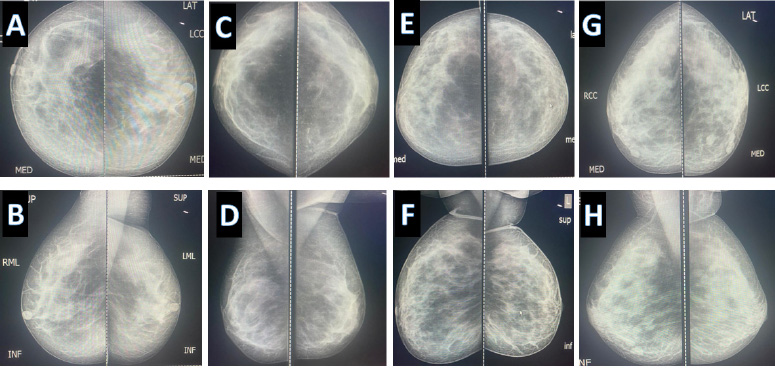

Wide diversity of “normal mammography” (A, B) same patient in craniocaudal and Mediolateral oblique view respectively, same applies to (C, D, E, F), and (G, H).